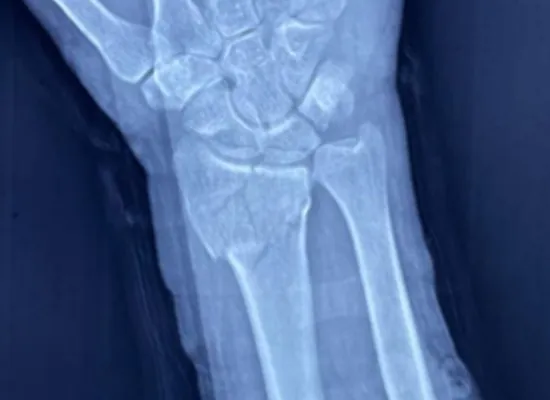

Mehhikos Tlalixtac de Cabrera osariigi haiglas viidi edukalt läbi distaalse raadiuse luumurru operatsioon VA distaalse raadiuse lukustusplaadi abil, mille pakub Hiina juhtiv ortopeediliste implantaatide tootja CZMEDITECH.

53-aastane patsient sai pärast kukkumist randmeluu raadiuse murru. Meditsiinimeeskond valis sisemise fiksatsiooni, kasutades muutuva nurga all asuvat distaalse raadiusega lukustusplaati, tagades anatoomilise reduktsiooni ja varajase mobilisatsiooni.

See juhtum näitab, kuidas lukustusplaadi fikseerimine võib taastada liigese stabiilsuse ja funktsiooni, eriti distaalse raadiuse keeruliste intraartikulaarsete murdude korral.

Operatsioonijärgne hindamine näitas suurepärast joondust, stabiilset fikseerimist ja varajast liigese liikumist.

VA distaalse raadiusega lukustusplaat (25,5 mm, 2-ava)